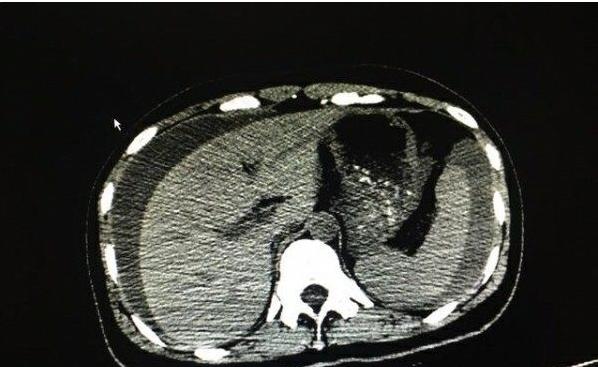

第一时间完善腹部CT,一切原因真相大白!

患者的腹腔内有大量的液体聚集,而据其丈夫代诉:“她之前好好的,没有任何疾病!”